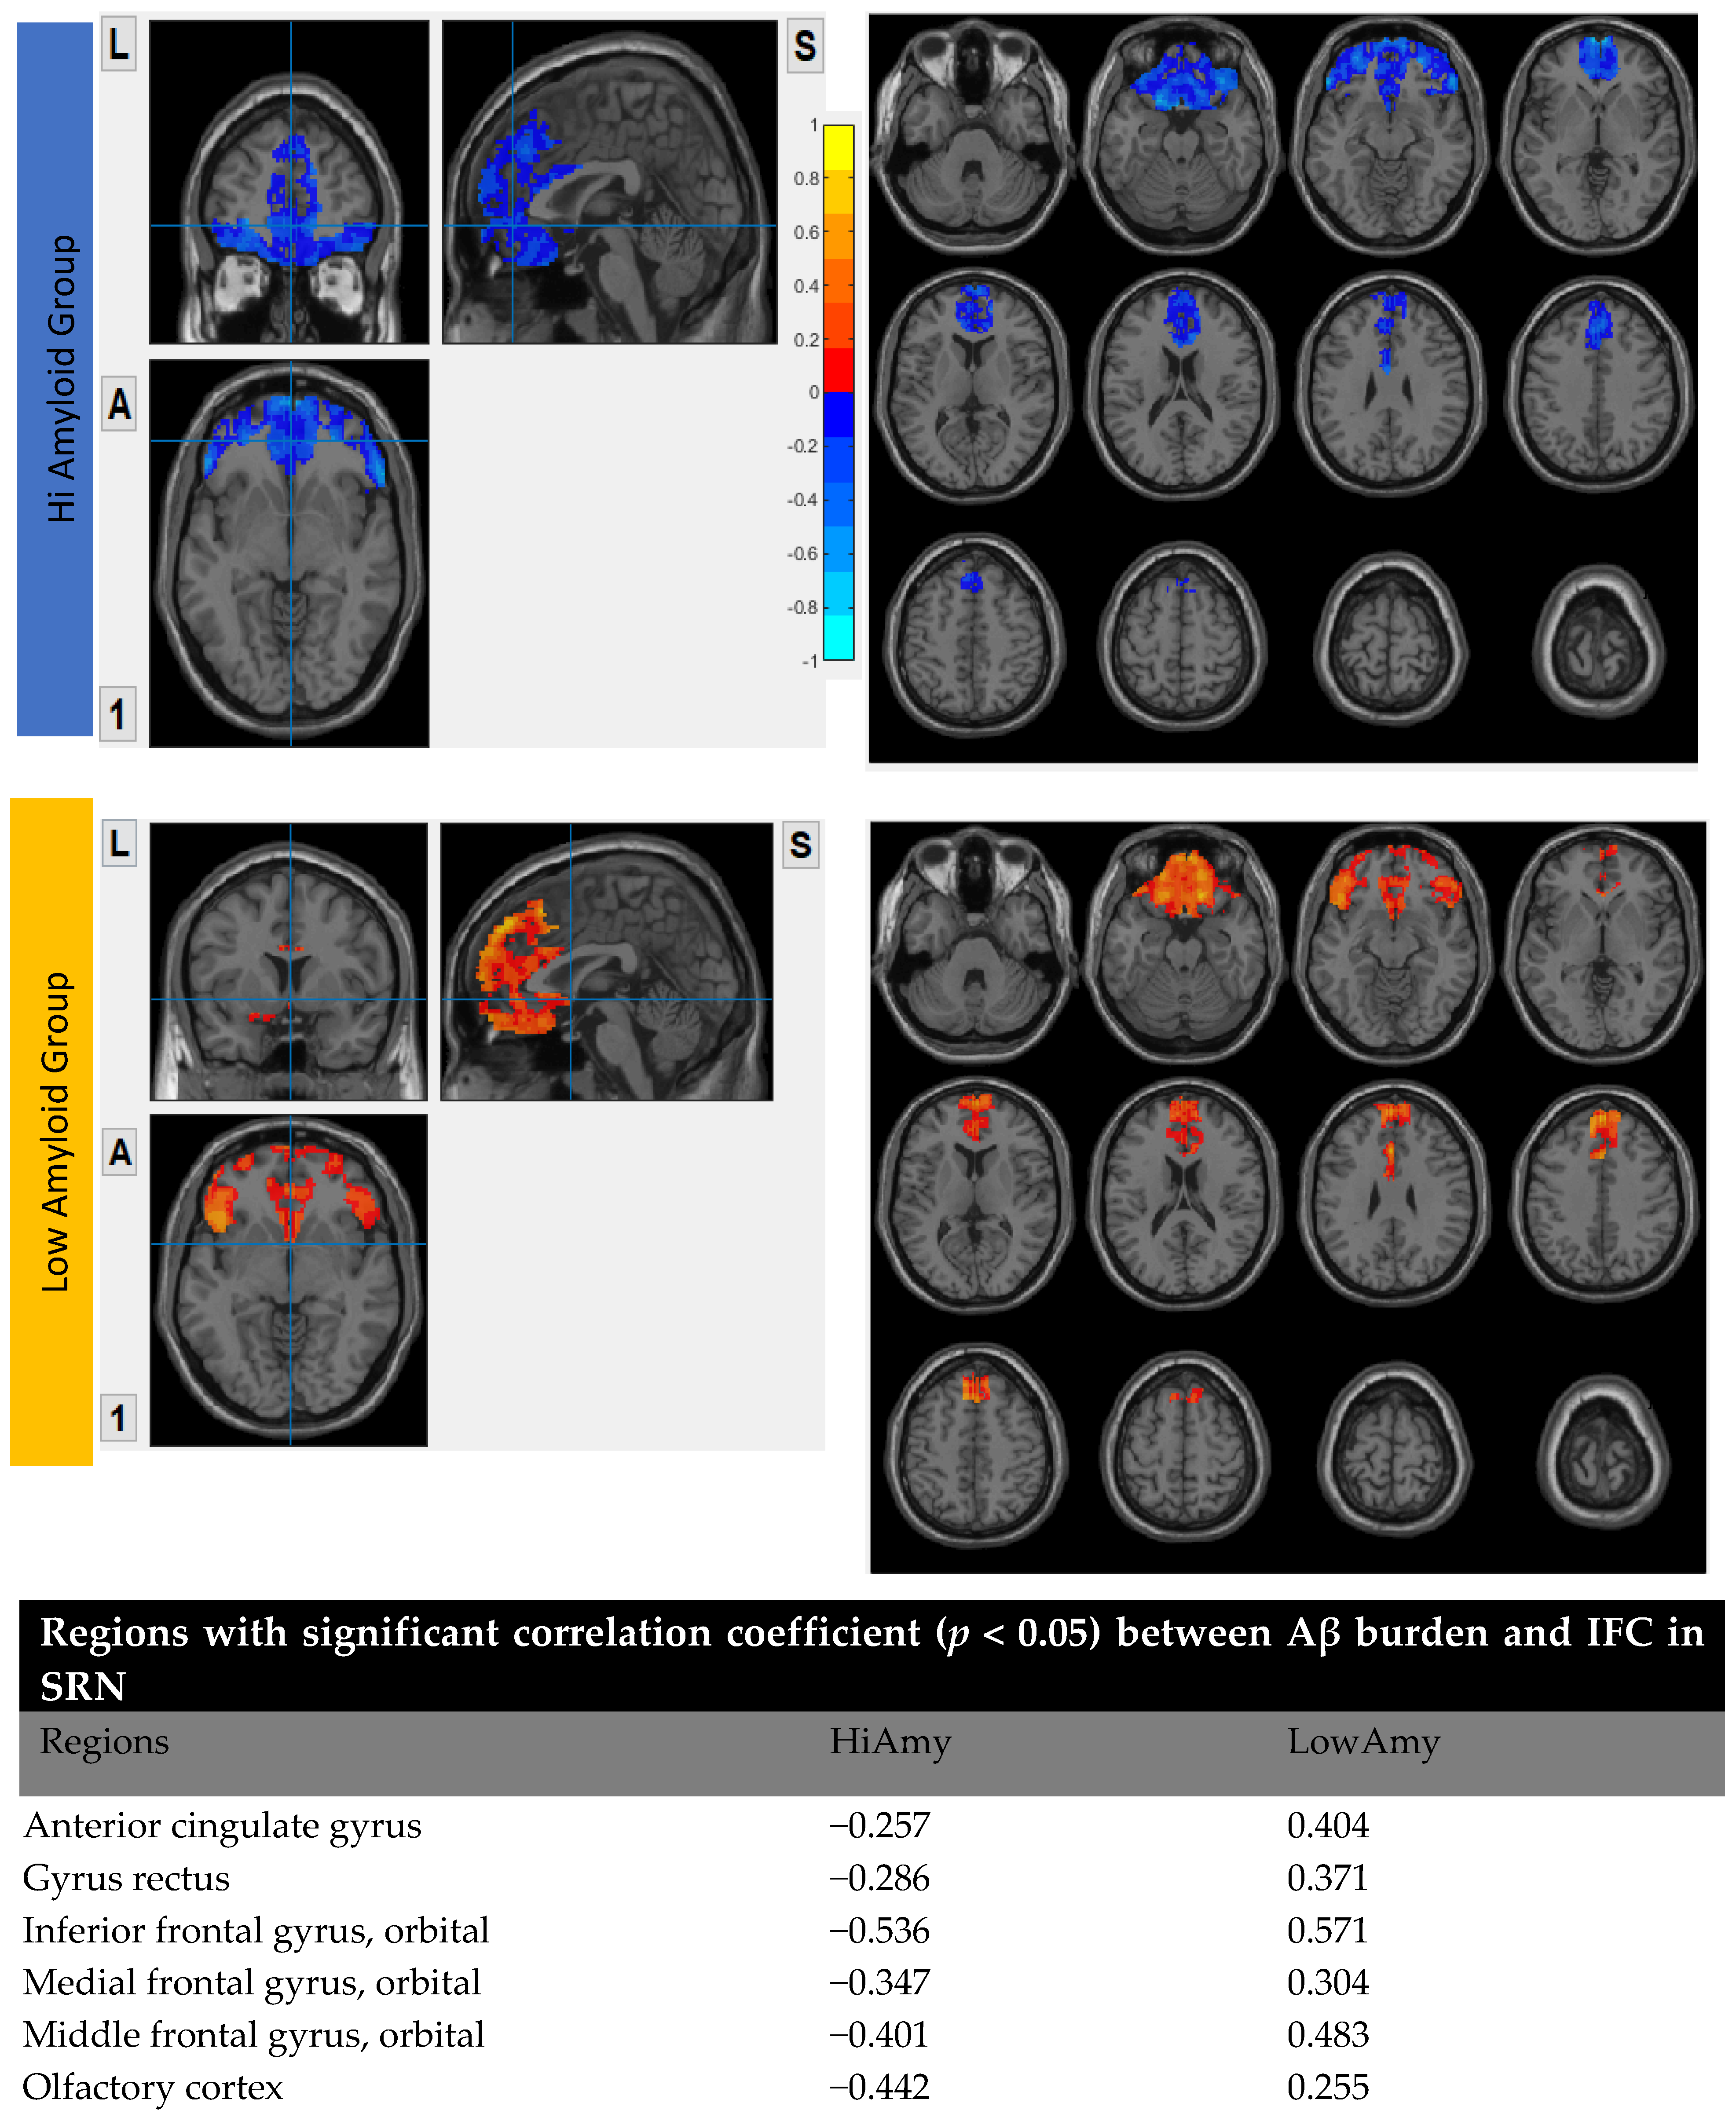

7.4. Within SRN